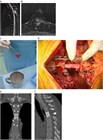

1. がんの既往のある患者が脊椎に痛みを訴えた場合、転移性脊椎腫瘍を念頭に置くことが推奨される(推奨度1)

1. 転移性脊椎腫瘍を疑った場合、全身の造影CTを撮影することが推奨される(推奨度1)

1. 転移性脊椎腫瘍と診断した場合、余命を評価することが推奨される(推奨度1)